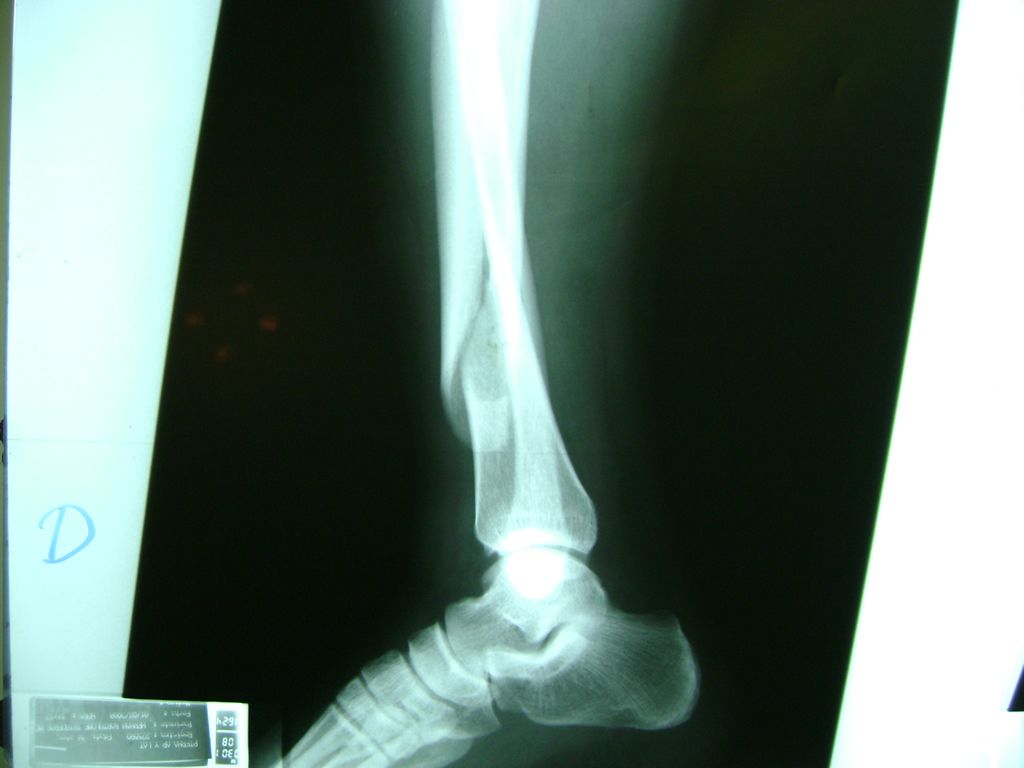

Cirugias en El Salvador - Perone y Tibia

La mayor parte de las roturas implican a la parte proximal del hueso (parte del hueso próximo a la rodilla) o a la parte distal (parte del hueso cerca del tobillo).

Debido a la fina cobertura de piel que recubre la tibia y el peroné, las fracturas generalmente son abiertas, es decir, el hueso roto rasga la piel, atravesándola. Las fracturas de tibia y peroné generalmente se producen por un fuerte impacto o torsión.